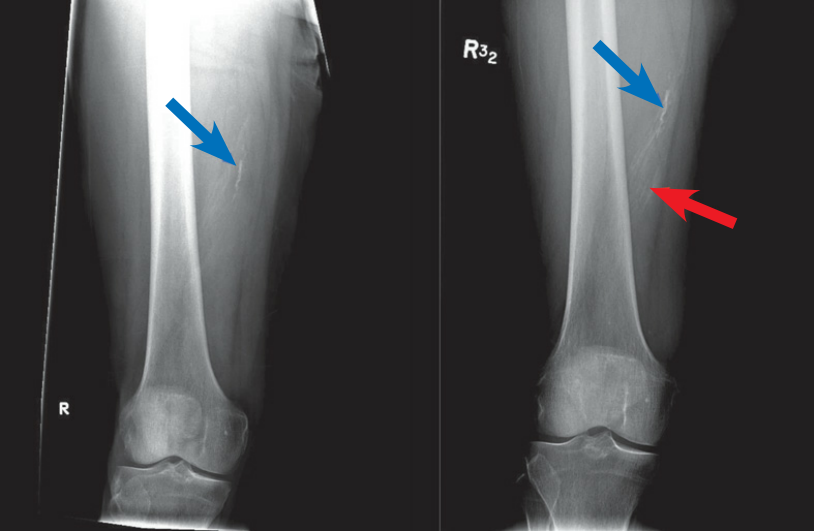

左图:X 线显示线状钙化影 (左蓝色箭头)。右图:随访 4 个月,可见钙化增多 (红色箭头),符合异位骨化。